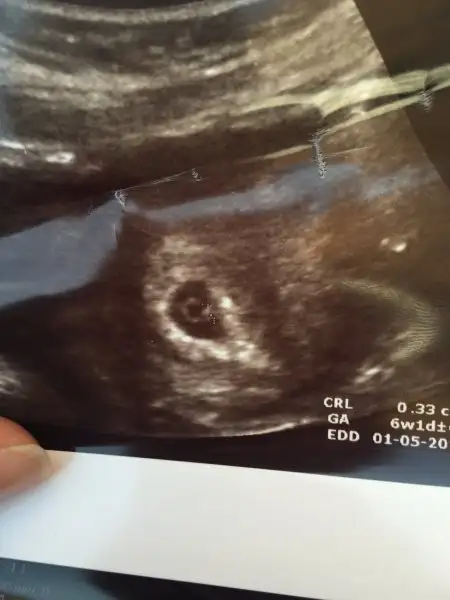

Teyzoşşşşşşşşşlar Slm biz bugun doktora gittik 5+6 olmamız gerekirken 6+1 göründü ultrasonda ve kalbimiz bile atmaya başlamış şükürler olsun ☺️ Derindende olsa duyduk çok dua etmiştim alın size ilk fotomuz teyzeler bi maşallahınızı alırız :nazar: bu arada hala çok gazım var karnım 3 aylık gibi :KK43: unuttum doktora sormayı Heycandan